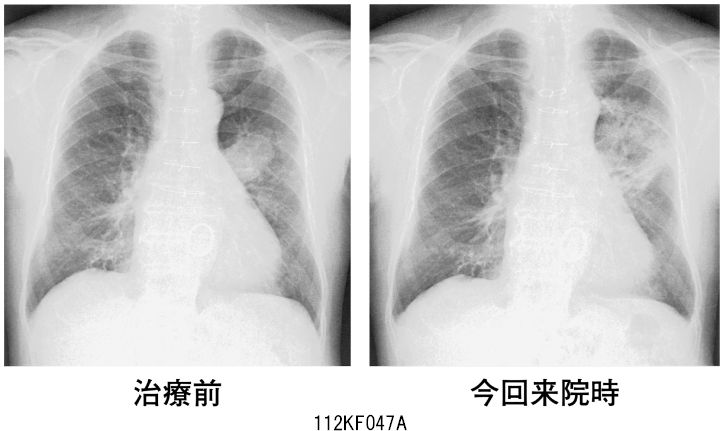

胸部X線の正常・異常画像を見極める〜日常診療で出合う境界症例, 112F47 | 医原性・化学物質による肺障害 国試 | テコプラ,

112F47 | 医原性・化学物質による肺障害 国試 | テコプラ, 一般撮影|大阪母子医療センター,

一般撮影|大阪母子医療センター, 胸腺腫(きょうせんしゅ Thymoma) – 呼吸器疾患 - 神戸きしだ,

胸腺腫(きょうせんしゅ Thymoma) – 呼吸器疾患 - 神戸きしだ, 一般撮影|大阪母子医療センター,